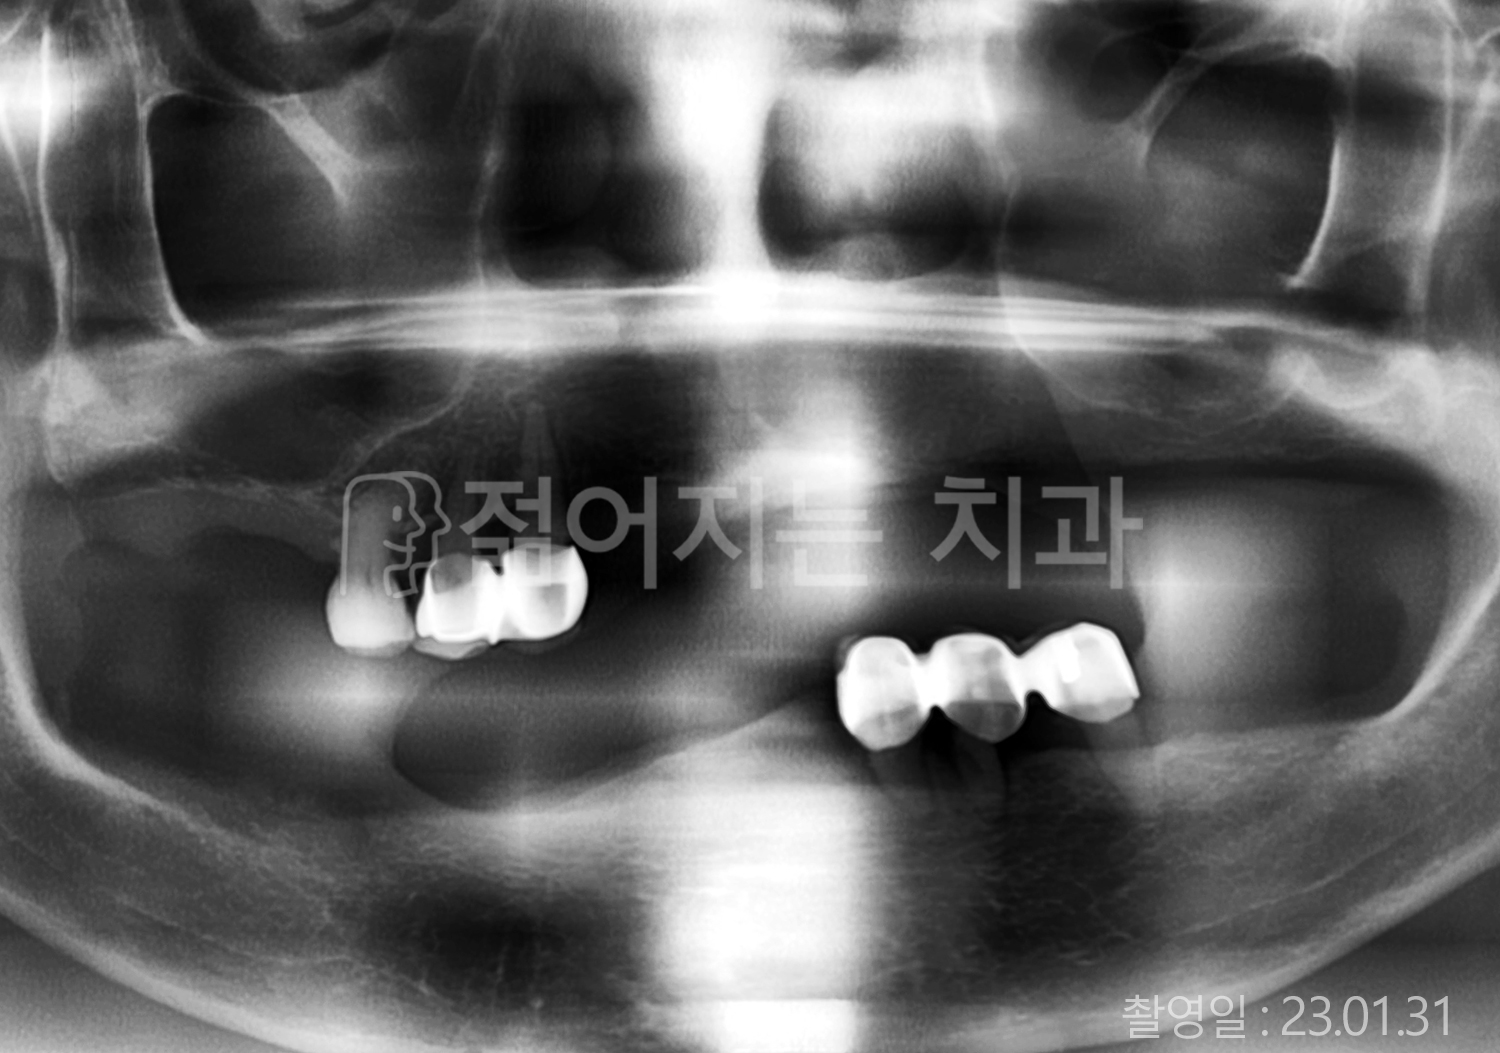

• 60대 고혈압, 고지혈증 전체치아 10개 이상 임플란트

• 70대 전체치아 10개 이상 임플란트

• 60대 전체치아 10개 이상 임플란트

• 50대 전체치아 10개 이상 임플란트

• 50대 고혈압, 고지혈증 전체치아 10개 이상 임플란트

• 60대 고혈압, 당뇨, 고지혈증 전체치아 10개 이상 임플란트

• 80대 고혈압, 당뇨, 골다공증 전체치아 10개 이상 임플란트

• 60대 고혈압 전체치아 10개 이상 임플란트

• 60대 고지혈증 전체치아 10개 이상 임플란트

• 60대 당뇨 전체치아 10개 이상 임플란트